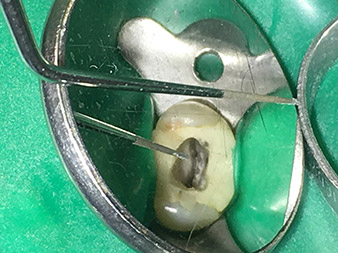

Oltre a metodi e a trattamenti diagnostici efficaci, l'utilizzo degli ultimi ausili e strumenti tecnici è un contributo importante al successo della cura del paziente. Il dott. Shahrad Nouraie Ashtiani e il suo team nello studio a Brema, Germania, tratta fino a dieci casi di endodonzia alla settimana. Il desiderio del paziente di un trattamento che sia il meno traumatico possibile, combinato con una prognosi di successo rappresentano una sfida quotidiana per il dentista e il chirurgo odontoiatrico specialista.

Grazie all'utilizzo estensivo della gamma di strumentazione W&H per endodonzia a ultrasuoni, il dott. Nouraie Ashtiani è in grado di eseguire il trattamento dei canali radicolari in modo più efficace e con minore stress per il paziente. L'odontoiatra esperto può fare fronte con facilità anche alle situazioni più difficili. In una recente intervista, lo specialista in endodonzia ci ha parlato delle particolari caratteristiche che contraddistinguono gli strumenti W&H e ha citato i possibili rischi che comporta il trattamento dei canali radicolari.

Foto: Dott. Nouraie Ashtiani, Brema